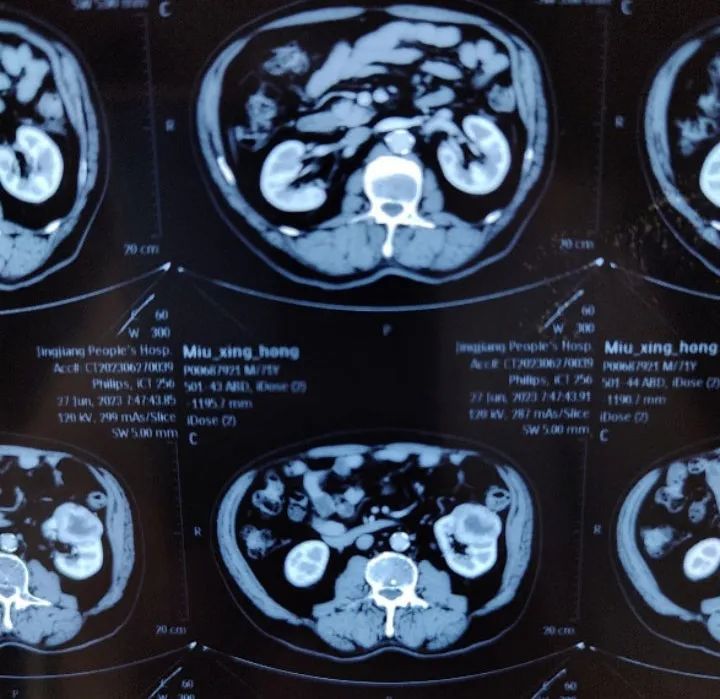

患者男性,71岁,主诉:发现左肾肿瘤2月余。患者近2月前因“右上肢麻木乏力1天”入院,伴口齿不清,2023-6-22查头颅MRI提示:桥脑偏左侧急性腔梗灶,双侧额顶叶皮层下、基底节区、放射冠、半卵圆中心区及侧脑室周围缺血、腔梗、腔隙灶。2023-6-27腹部增强CT提示:左肾占位,考虑透明细胞癌。诊断急性脑梗死,予以抗凝、降脂、活血等对症治疗,恢复可。既往高血压病史,现规律服用缬沙坦、氨氯地平治疗。此次会诊的目的:下一步治疗方案?手术治疗时机?是否需要新辅助治疗?

影像科周秀秀主治医师:该患者的头颅CT和MRI均提示脑干急性梗塞,血管造影提示粥样硬化表现,可观察到宽基底、大小约0.5cm的基底动脉瘤,可考虑行DSA检查以明确其分级。腹部增强CT影像检查提示左肾透明细胞癌可能大,目前脑梗及肾脏肿瘤诊断明确,建议患者脑梗发生3月后,再次复查头颅CT、腹部CT,评估身体康复及病情进展情况。

泌尿外科任吉忠教授:根据患者CT影像显示,肿瘤位于左肾中部,大小约4cm,可观察到病灶中央存在坏死区域,说明肿瘤生长速度较快,恶性程度较高,建议待脑梗病情稳定后,尽快进行手术治疗。为进一步保证患者安全,减少术中、术后出血及脑血管并发症风险,可预先完成双侧肾功能GFR检查,明确双侧肾脏功能情况。如对侧肾脏功能正常,可优先考虑左肾根治性切除术方案,有助于保证肿瘤控制效果,同时减少围手术期并发症风险。术后可以早期恢复抗凝治疗,定期进行手术局部及脑血管情况复查。